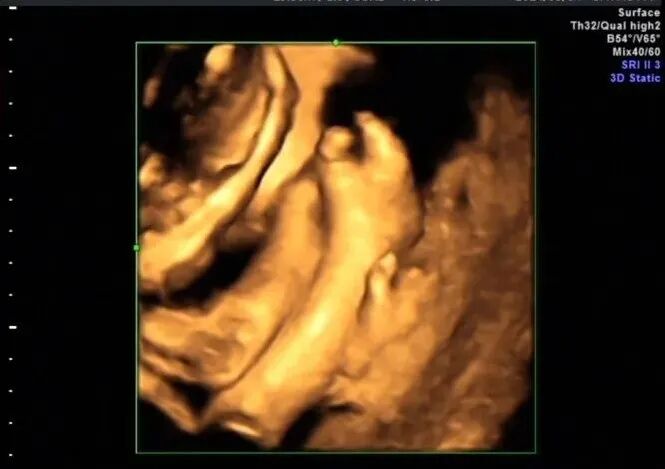

再看脚也不对劲,马上启动三维超声,下图是三维超声表现

手脚都有问题,呈龙虾爪样,非常典型的手裂足裂,胎儿父母没有啥疾病